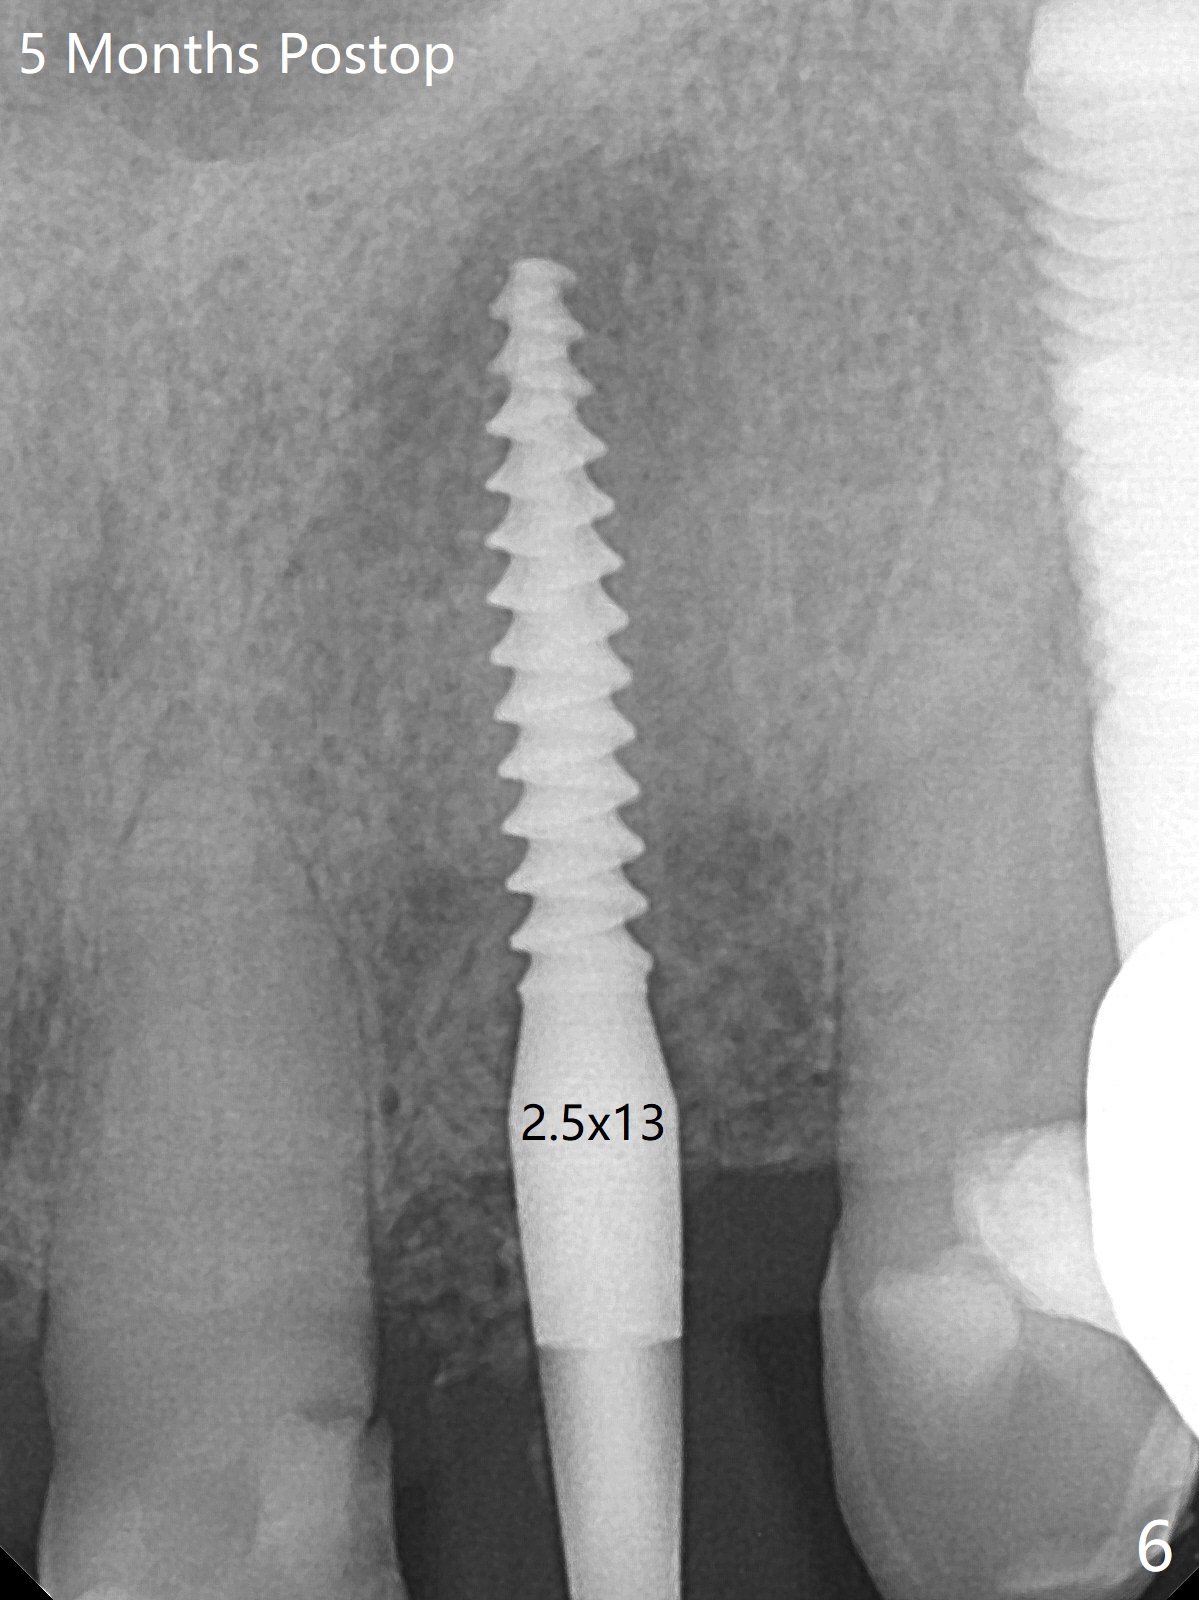

After undersized drilling in depth at #10 (2.2x13 mm (10.5 mm offset), Fig.1), a 2.5x13 mm 1-piece implant is placed (Fig.2,3), as compared to the design (Fig.3'). Following 3 more turns of the implant (~ 20 Ncm), bone graft and heavy buccal reduction of the coronal end of the abutment, an immediate provisional is bonded to the tooth #9 (Fig.4) and splinted to the tooth #11 with a twisted wire (Fig.5). To increase stability and reduce reduction, a 3 mm 1-piece implant could be used with 15 degree abutment. The implant remains stable 5 months postop (Fig.6). The implant seems to be flexible before heavy occlusal reduction; note the periimplant micro-space (Fig.7). The patient is a bruxer. The implant crown seems to be minimally mobile 2 months post cementation (Fig.8, without treatment). 牙冠粘固后1年1个月软硬组织正常(图九)。